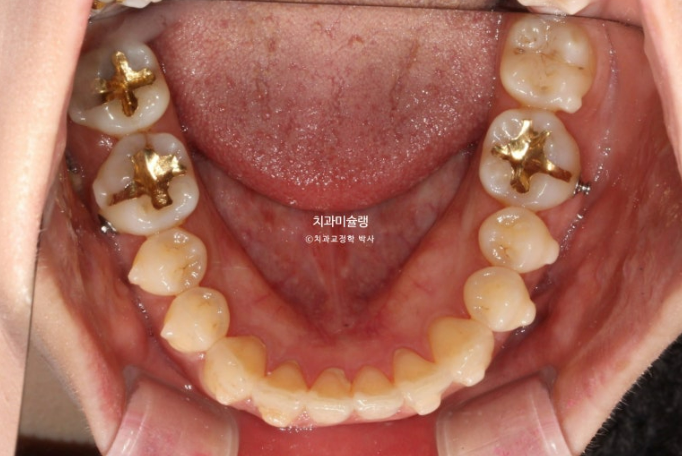

아래 큰어금니는 안으로 쓰러져 있습니다.

좌측에는 가위교합이 소구치에 하나 대구치에 하나 총 2군데 있습니다.

교합을 담당하는 어금니 중 절반이 가위교합 상태이니, 좌측으로 씹기가 힘든 상태입니다.